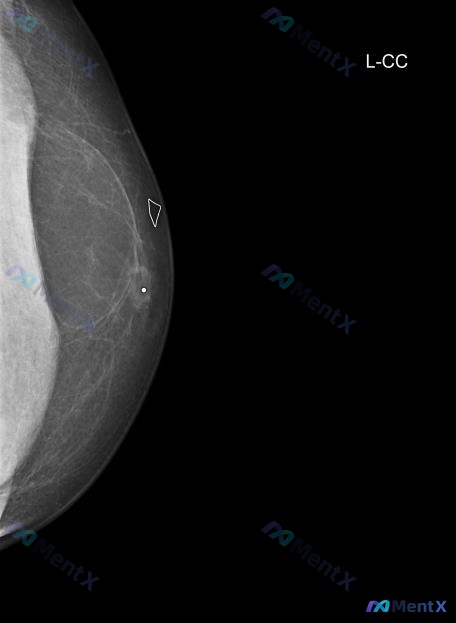

49岁男性左侧乳腺可触及肿块,影像有高密度结节+金属标记,最可能是什么?

- 钼靶(L-CC位):

- 脂肪型乳腺(ACR a型)

- 外侧象限见边界清楚的圆形/卵圆形高密度结节

- 结节中心似乎有高密度钙化或金属标记物(白色圆点)

- 周围有纤维组织牵拉,但整体边缘尚清晰

- 皮肤、腋窝(部分显示)未见明显异常

📋答案:综合考虑,最可能的是**伴有金属标记的术后脂肪坏死/油囊肿**。